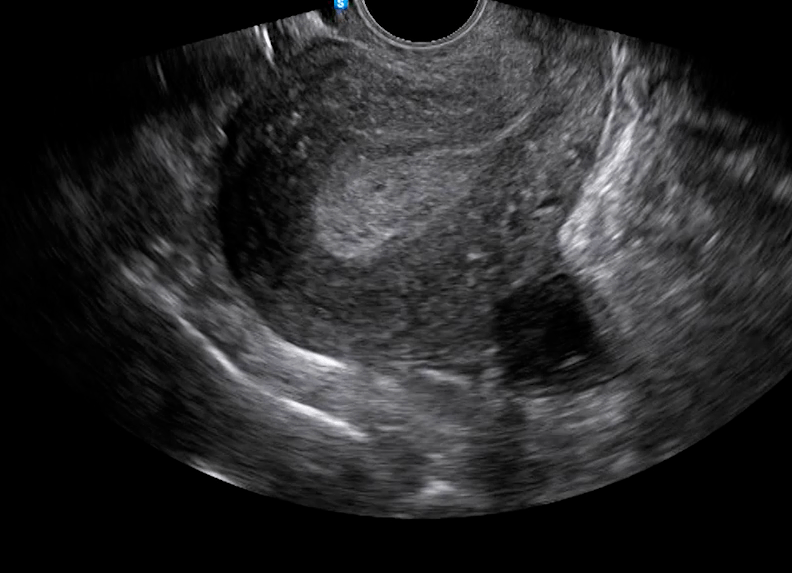

- Ultrasound Transvaginal: Mengukur ketebalan endometrium.